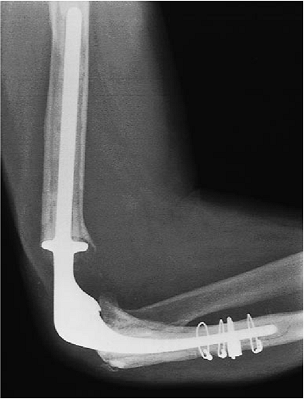

underwent joint replacement arthroplasty in 1980, but the replacement

loosened and was revised in 1988. This implant also loosened, migrating

proximally and the tip eroding anterior (Fig. 19-29). With the technique described earlier, an allograft was used to replace the proximal ulna (Fig. 19-30). Bone graft was placed behind the anterior flange and a 150-cm humeral component was inserted down the humeral canal (Fig. 19-31). The patient has excellent motion 1 week after surgery. The radiograph shows a well-fixed implant (Fig. 19-32).

Figure 19-29. AP (A) and lateral radiographs (B)

of a patient after two failed revision procedures showing the resurfacing implant eroding through the anterior proximal portion of the midhumerus. The lateral view also shows that the proximal ulna is completely eroded and that both the components are loose. |

![]() |

|

Figure 19-30.

An allograft has been used to replace the proximal ulna. The allograft has been secured with a semitubular plate with single cortical screws. The screws are stabilized with cement. |

Figure 19-31. A,B: The humeral component is inserted and stabilized with a bone graft behind the flange of the prosthesis.

Figure 19-32. A,B:

Five days after surgery the patient has very good early motion. The radiograph shows a well-fixed implant with a range of motion between 40 and 110 degrees at 5 days. |